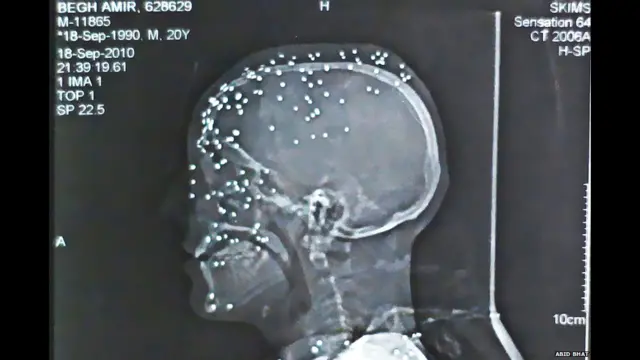

भारत प्रशासित कश्मीर में सुरक्षा बल अकसर पेलेट गनों यानी छर्रे वाली बंदूकों का इस्तेमाल करते हैं. इनसे जान तो नहीं जाती लेकिन कइयों की रोशनी जरूर चली गई है.